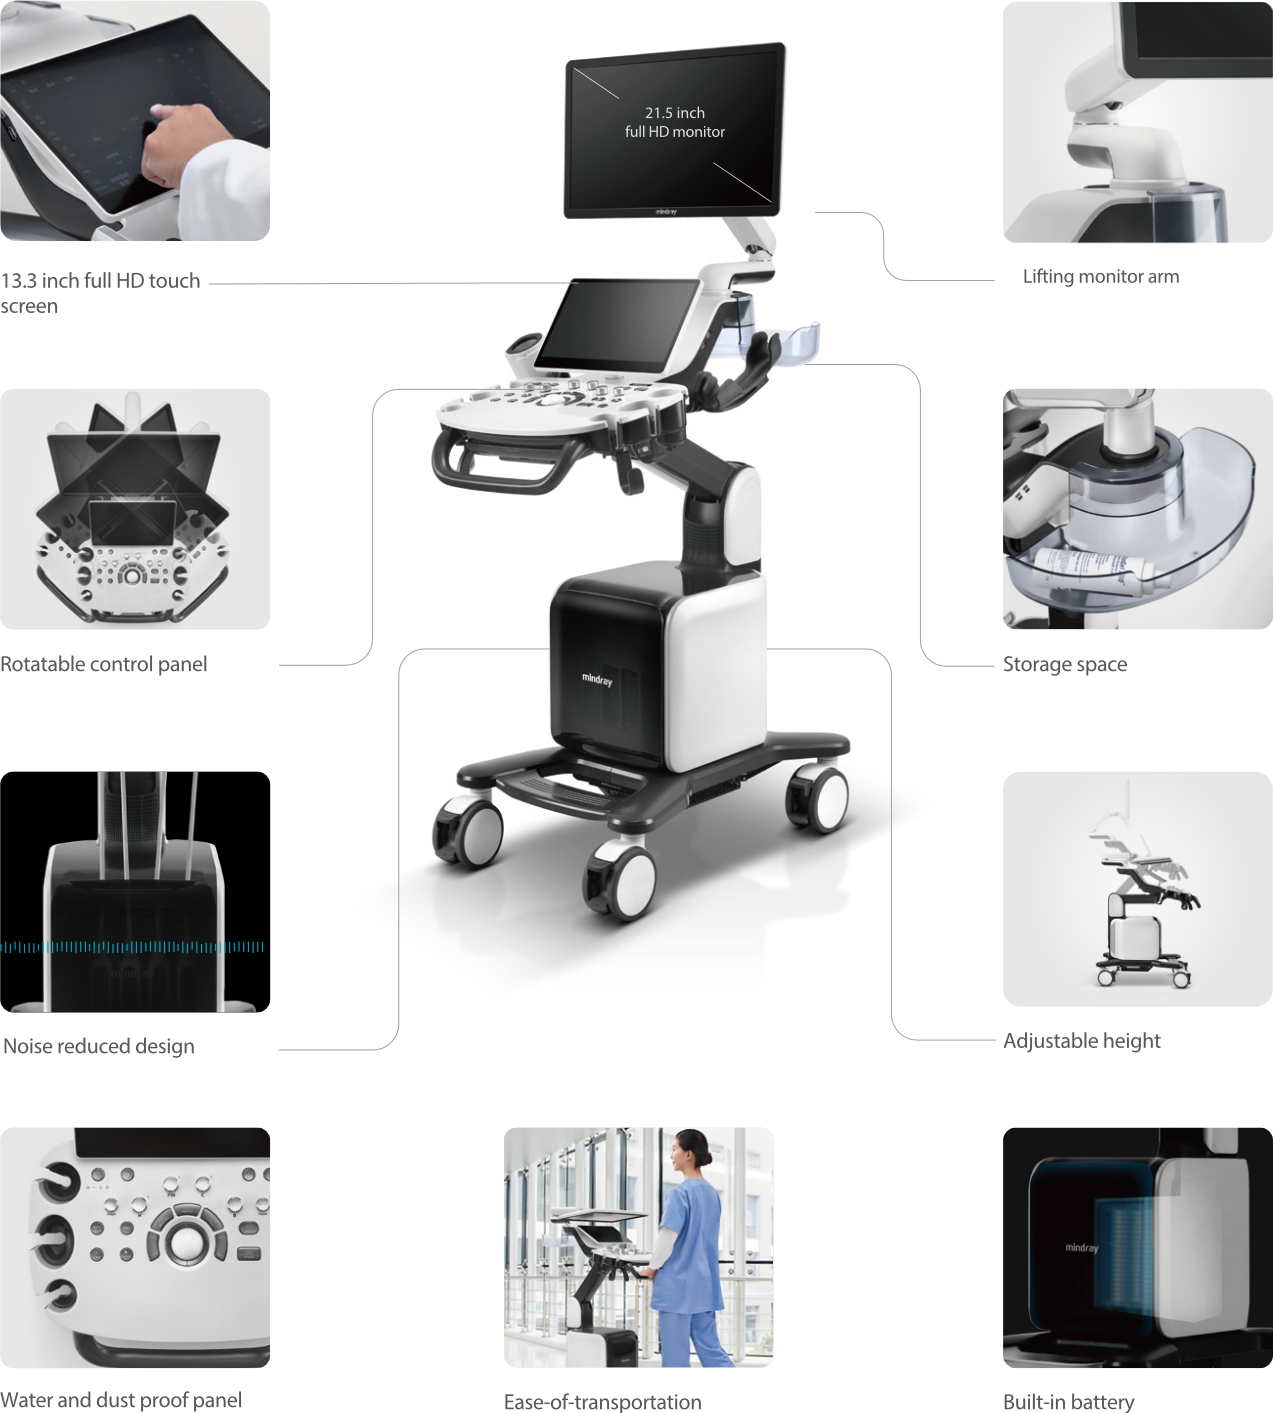

Nuewa i8

El Nuewa I8, ofrece una claridad de imagen inigualable, elevando tu confianza y eficiencia a nuevas alturas. Diseñado con el máximo cuidado, minimiza la fatiga y maximiza la conveniencia a lo largo del proceso de operación.

Impulsado por la innovadora plataforma ZST + y un conjunto completo de soluciones inteligentes, el Nuewa I8 ofrece una claridad de imagen inigualable, impulsando tu confianza y eficiencia a nuevas cotas. Diseñado con la máxima atención al detalle, minimiza la fatiga y maximiza la comodidad durante todo el proceso quirúrgico.

RESONA i9

Resona I9 es un sistema de ecografía de aplicación general con características notablemente innovadoras. Estas innovaciones se desarrollan sobre la base de conocimientos profundos en situaciones clínicas complejas, para proporcionar respuestas precisas y oportunas, una gran eficiencia y una notable experiencia de usuario.

Se puede ajustar para utlizar mejor el espacio

Satisface fácilmente las distintas necesidades de exploración

- Diseño del panel de control inteligente y específico para exámenes clínicos con teclas especiales de tinta electrónica

- Diseño innovador y adaptable para diferentes situaciones clínicas